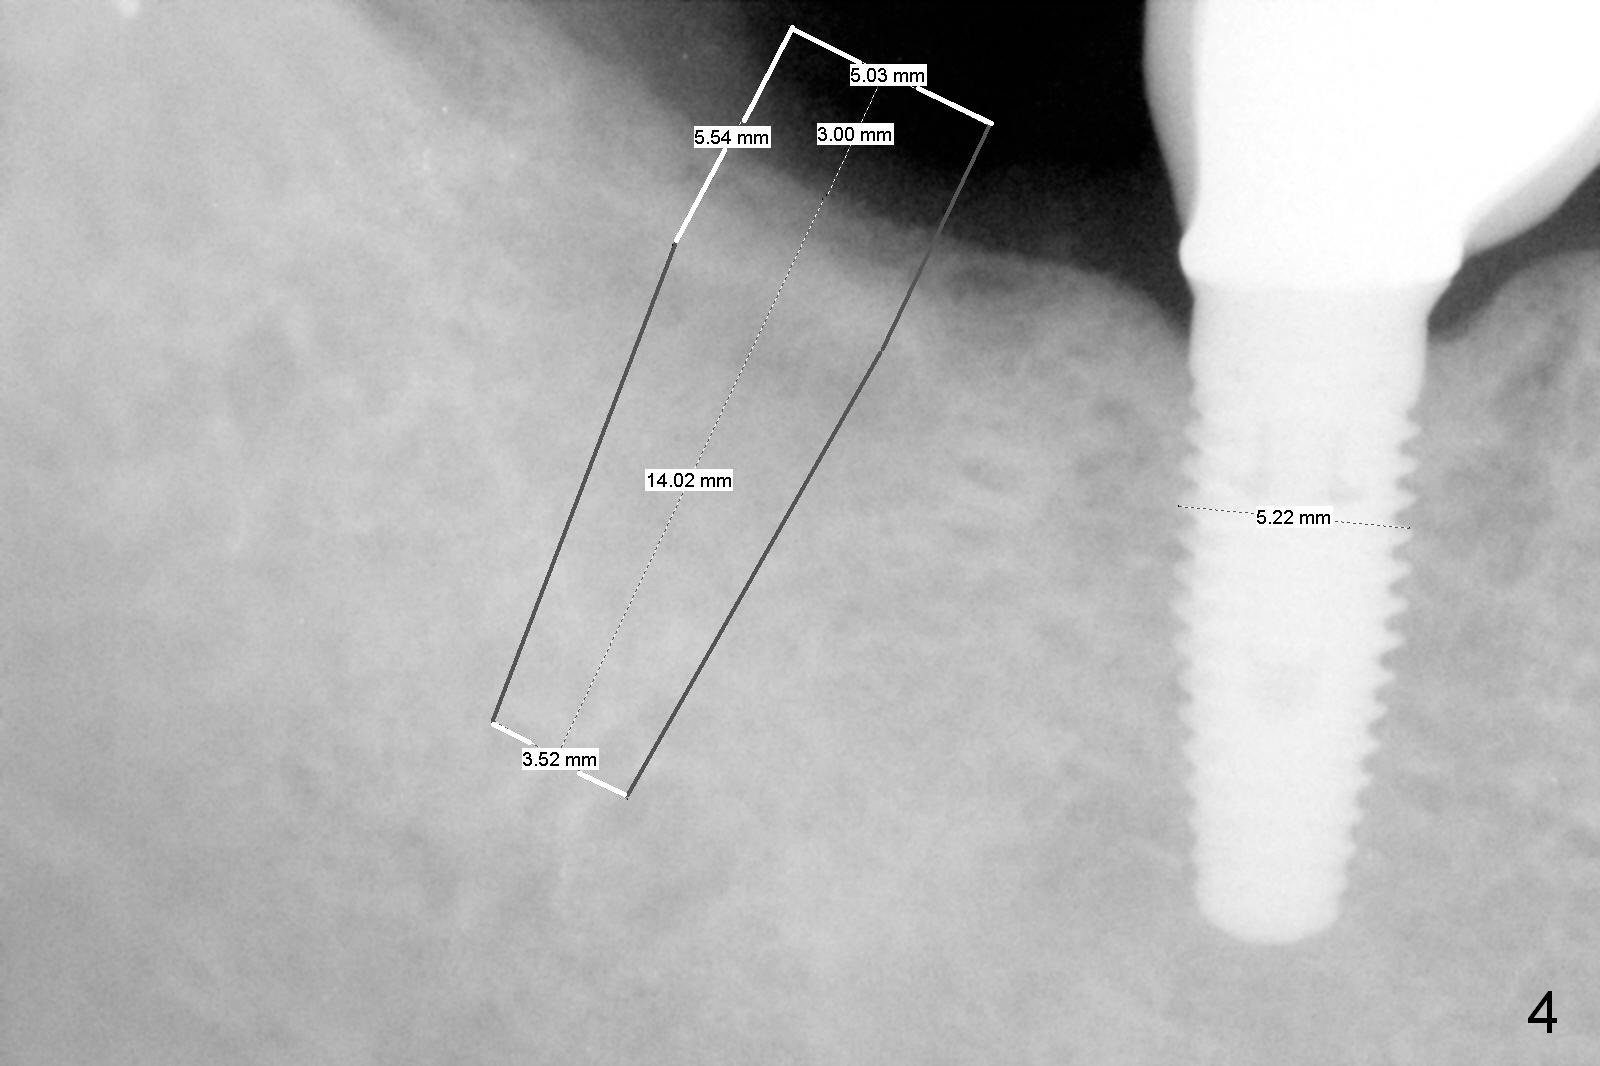

A 62-year-old woman requests #31 implant placement ~ 1 year post extraction (Fig.1). The opposing tooth (#2) appears to have not supraerupted. The socket outline at #31 is visible (Fig.2,3 red dashed line). The initial osteotomy (green) should bisect the socket and be perpendicular to the posterior mandibular slope (pink). The stopper is set at 10 mm with sufficient clearance from the superior border of the Inferior Alveolar Canal (yellow dashed line). Take PA for confirmation and make necessary adjustment. The implant is either 5x17 mm (tissue-level) or 5x13 or 14 mm (bone-level).